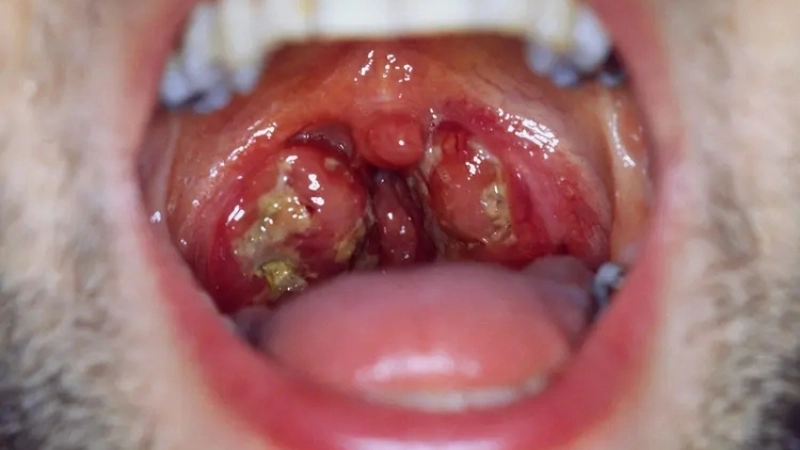

• Sore throat with white patches on the tonsils, occasionally causing difficulty swallowing and tender throat glands.

Image description of Infectious Mononucleosis (Glandular Fever)

Infectious Mononucleosis, also called glandular fever, is a contagious viral infection primarily caused by the Epstein-Barr virus. It often leads to fatigue, sore throat, and swollen lymph nodes, especially in adolescents and young adults.